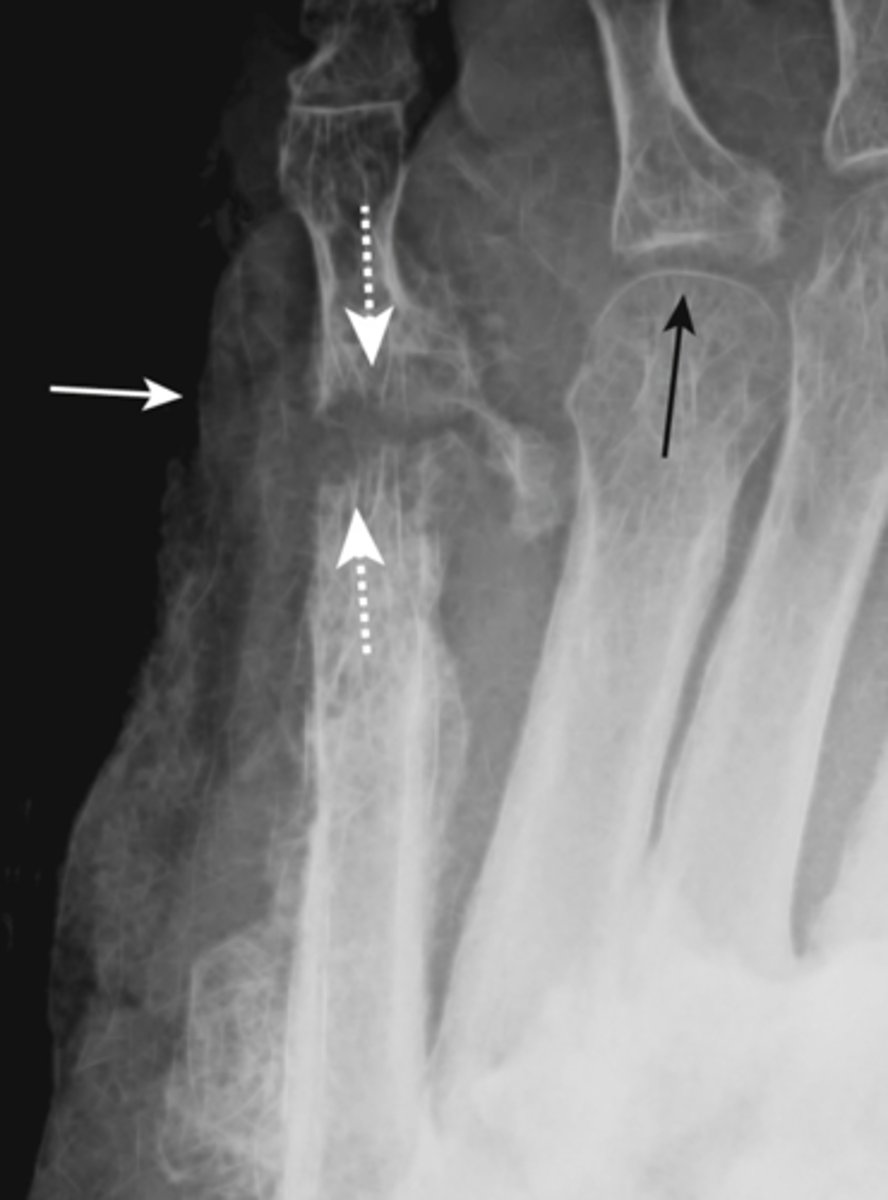

gout

inflammatory changes incited by deposition of calcium urate crystals in joint, most commonly metatarsal-phalangeal joint of great toe

- sharply marginated erosion w sclerotic border "rat bites"

- joint space narrowing

- tophi- collections of urate crystals

- olecranon bursitis